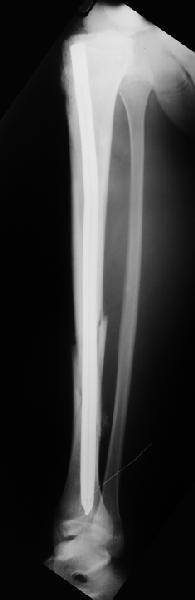

Вчера первый раз синтезировали голень гвоздем Fixion.

Спиральный оскольчатый перелом, ниже середины, у молодого парня. Сделали "классический" вариант гвоздя, который еще без винтов. Получилось все легко. Не торопясь, сделали операцию минут за 20. См. фото.

Дорогой Александр. Имею скромный опыт использования системы Fixion при переломах плеча, бедра и тибии. Всего 18 наблюдений с сентября 2006 г. Результаты отличные. Гвоздь индивидуален для каждого медуллярного канала. Легко имплантируется как в узкий, так и в деформированный канал. Это позволяет применять метод интрамедулярного остеосинтеза без ненужных потерь времени операции, флюороскопии и реально снижает крвопотерю и операционный риск. Удаление происходит без проблем. Особенно интересны больные с ипсилатеральными переломами бедра и голени.

В отношении ранней нагрузки при спиральных переломах лучше не торопиться. По данному случаю необходимо достигнуть исчезновения щели между штифтом и внутреним кортексом по Rg. А так картинка прекрасная - и длина сегмента и репозиция. Можно поздравить, коллега!